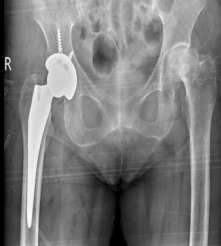

▲患者术后影像学检查

术后阿嬷恢复良好

术后第二天下地行走

一周康复出院!